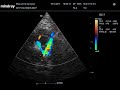

Сердце